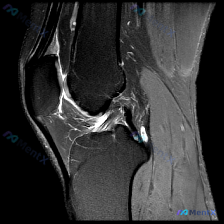

看到一张很有意思的读片病例,整理出来和大家分享,这个病例太能体现诊断思维的重要性了。 病例基本情况 用户提问:What diagnosis does the picture indicate?Chondral abnormality 提供的是一张膝关节MRI矢状位T2(或质子密度)加权图像,图像质量...

拿到这张膝关节MRI T2加权矢状位图像,用户提示要找「软骨异常」,整理了完整的读片思路分享给大家。 一、影像基础信息 这是膝关节正中矢状位附近的T2加权序列,水成像特征清晰,高信号对应积液/水肿,能清楚看到髌骨、髌腱、前后交叉韧带和部分胫骨平台结构。 二、系统阅片结果 1. 骨骼结构:股骨远端、胫...

刚整理了一份有意思的膝关节MRI读片病例,核心问题是单张T1矢状位图像提示「软骨异常」,这里把整个分析思路整理出来和大家交流。 一、病例基本影像信息 这是一张膝关节正中偏内侧矢状位的T1加权MRI图像,图像质量良好,无明显伪影,可清晰观察髌骨、股骨远端、胫骨近端、后交叉韧带及半月板结构。 二、系统性...

最近看到一个读片问题:给出了一张膝关节MRI冠状位T1加权像,怀疑存在软骨异常,要分析可能的观察结果。我整理了完整的分析思路,分享给大家。 一、影像基本情况 这是一张清晰的膝关节MRI冠状位T1加权像,切面位于关节中后部,可以看到股骨远端内侧髁、胫骨近端内侧平台、内侧半月板体部以及内侧副韧带结构,图...

病例读片讨论:临床提示软骨异常,MRI怎么看? 看到一个有意思的读片病例,临床提示存在软骨异常,只有一张膝关节MRI轴位T2加权像,整理了分析思路和大家分享。 病例影像信息 本次仅提供单张膝关节MRI轴位T2加权像,影像评估结果如下: 1. 骨性结构:股骨滑车、股骨内外髁形态正常,无骨折,无明显骨髓...